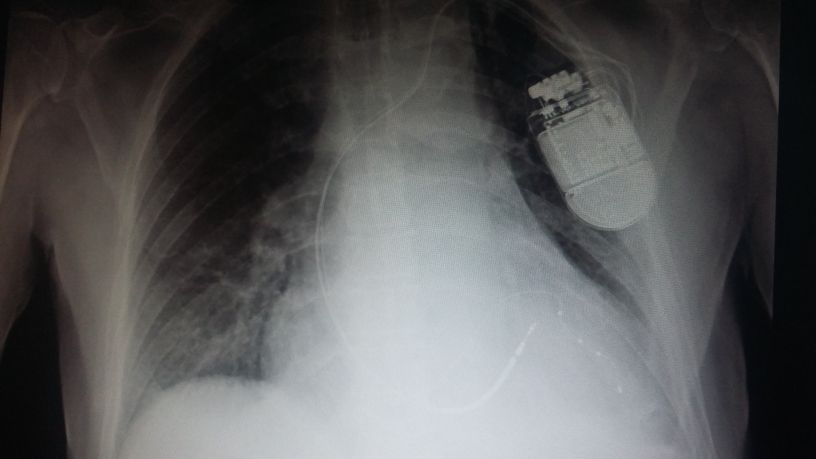

E' esperto in disturbi del ritmo cardiaco quali le bradicardie, dovute a blocchi atrioventricolari o a disfunzioni del nodo seno-atriale, la fibrillazione ed il flutter atriale, le tachicardie sopraventricolari, le aritmie ventricolari quali extrasistolie o tachicardie ventricolari congenite ed acquisite. Inoltre si occupa di impianto e programmazione di device cardiaci quali pacemaker, defibrillatori, defibrillatori biventricolari automatici (ICD – BIV) e loop recorder (dispostivi per il monitoraggio cardiaco a lungo termine impiantabili) e delle ablazioni transcatatere delle aritmie.